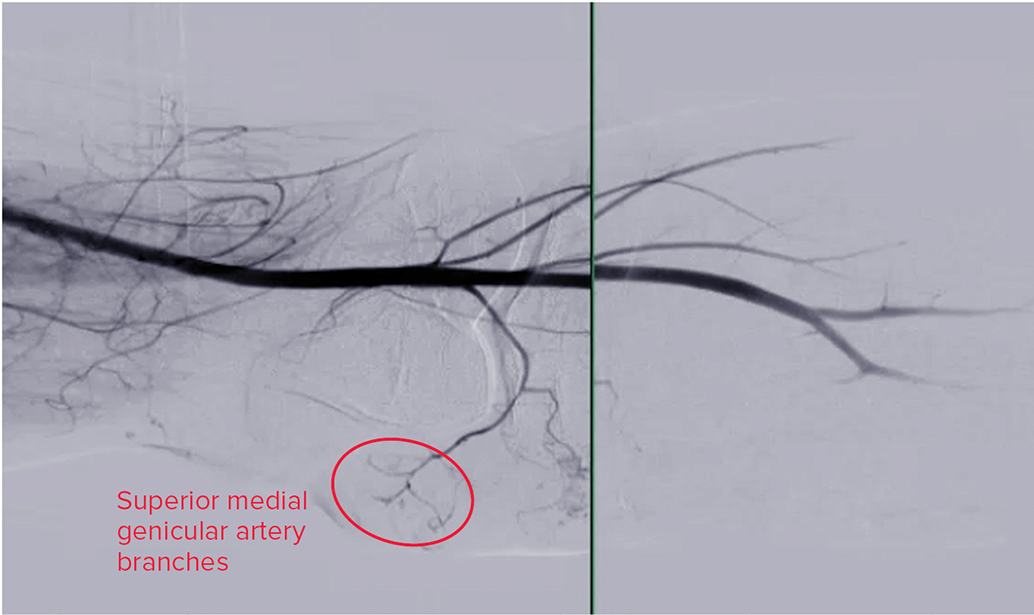

• Data review presents geniculate artery embolization as an emerging minimally invasive technique for knee OA

Osteoarthritis is characterized by the breakdown of articular cartilage, subchondral bone remodeling, osteophyte formation, and synovial inflammation, which leads to chronic pain and reduced quality of life.